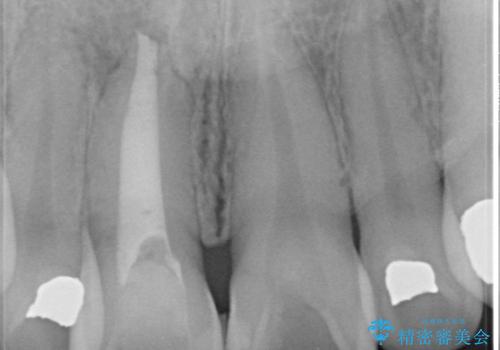

器具が破折して残ったままの前歯

お痛みは無く、たまに異和感があるとのことでレントゲン撮影をすると、以前根の治療をされた際の器具が破折したまま残っていました。

破折した器具を除去したのち、根管治療、ファイバーコア築造、セラミッククラウンの製作を行いました。

セラミックは、2本行う事でより自然な仕上がりとなり、患者様もご満足していただけました。